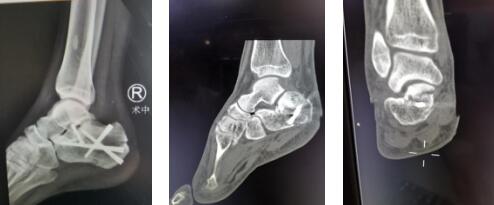

1.1右跟骨术前CT及X线

1.4内固定术后情况

6月30日,充分的术前准备后,曹主任、李亮医生手术团队为患者进行距下关节镜双跟骨骨折撬拨复位内固定术。先进行右跟骨骨折复位内固定术,取外踝尖下两处不到0.5cm切口,进入距下关节镜,检查关节,见右跟骨粉碎性骨折,部分骨折块塌陷,关节腔内淤血块。以刨削器去除关节淤血及水肿滑膜,在关节镜辅助下骨折复位,将塌陷的骨折块撬拨复位,恢复跟骨长宽高、关节面的平整及内翻畸形,多枚克氏钉临时固定,再次关节镜检查复位满意后拧入螺钉固定。随后又进行了关节镜下左跟骨复位内固定手术。